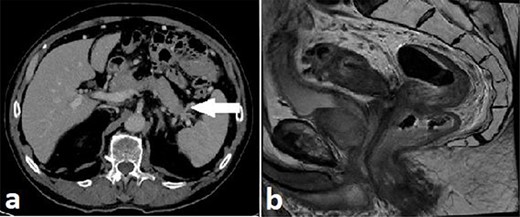

Routine staging for rectal cancer was performed. Magnetic resonance imaging (MRI) of the pelvis revealed an anterior rectal mass 7–8 cm from the anal verge with invasion into the seminal vesicles and at least three lymph nodes suspicious for metastases (cT4aN2). Computed tomography (CT) chest, abdomen and pelvis revealed enlarged nodes along the inferior mesenteric artery chain, but no definite metastatic disease was reported (Fig. 2). A 1.4 cm low attenuation hypo-enhancing mass in the distal pancreas occluding the splenic vein was reported as an incidental finding. Serum carcinoembryonic antigen (CEA) was 1.71ug/L and serum carbohydrate antigen 19-9 (Ca 19-9) was mildly elevated at 78u/ml.

Case A. Axial portal venous phase CT scan demonstrating hypo-enhancing distal pancreatic lesion encasing splenic vessels (a) and sagittal MRI pelvis demonstrating anterior low rectal tumour (b), staged as a cT4aN2Mx rectal adenocarcinoma.